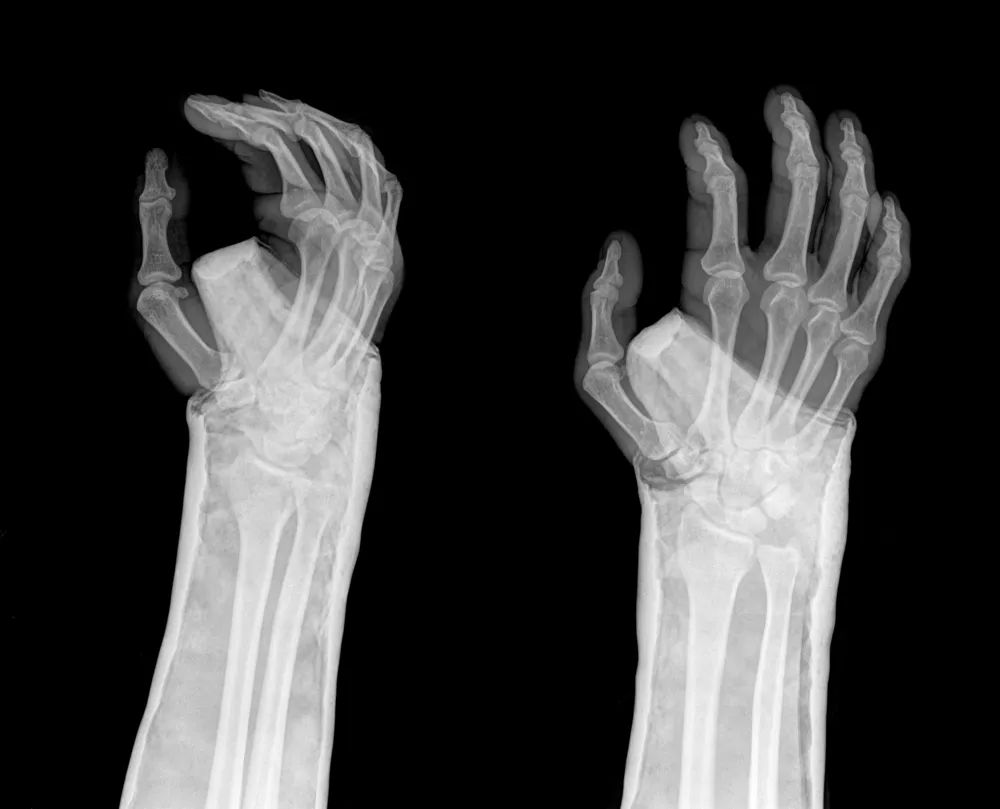

桡骨远端关节面呈由背侧向掌侧、由桡侧向尺侧的凹面, 分别形成掌倾角 (10°~15°) 和尺倾角 (20°~25°)。

图源:第八版外科书

典型畸形姿态即侧面看呈「银叉」畸形,正面看呈「枪刺样」畸形。X 线可见骨折远端向桡、背侧移位,近端向掌侧移位。

X 线拍片可发现典型的移位。当跌倒时, 腕关节屈曲、手背着地受伤, 可发生与上述相反的桡骨远端掌侧关节面骨折及腕骨向掌侧移位。